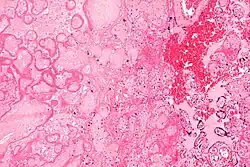

Micrograph of a placental infarct (left of image), a cause of intrauterine hypoxia. H&E stain.

Intrauterine hypoxia (also known as fetal hypoxia) occurs when the fetus is deprived of an adequate supply of oxygen. It may be due to a variety of reasons such as prolapse or occlusion of the umbilical cord, placental infarction, maternal diabetes (prepregnancy or gestational diabetes)[1] and maternal smoking. Intrauterine growth restriction may cause or be the result of hypoxia. Intrauterine hypoxia can cause cellular damage that occurs within the central nervous system (the brain and spinal cord). This results in an increased mortality rate, including an increased risk of sudden infant death syndrome (SIDS). Oxygen deprivation in the fetus and neonate have been implicated as either a primary or as a contributing risk factor in numerous neurological and neuropsychiatric disorders such as epilepsy, attention deficit hyperactivity disorder, eating disorders and cerebral palsy.[2][3][4][5][6][7]